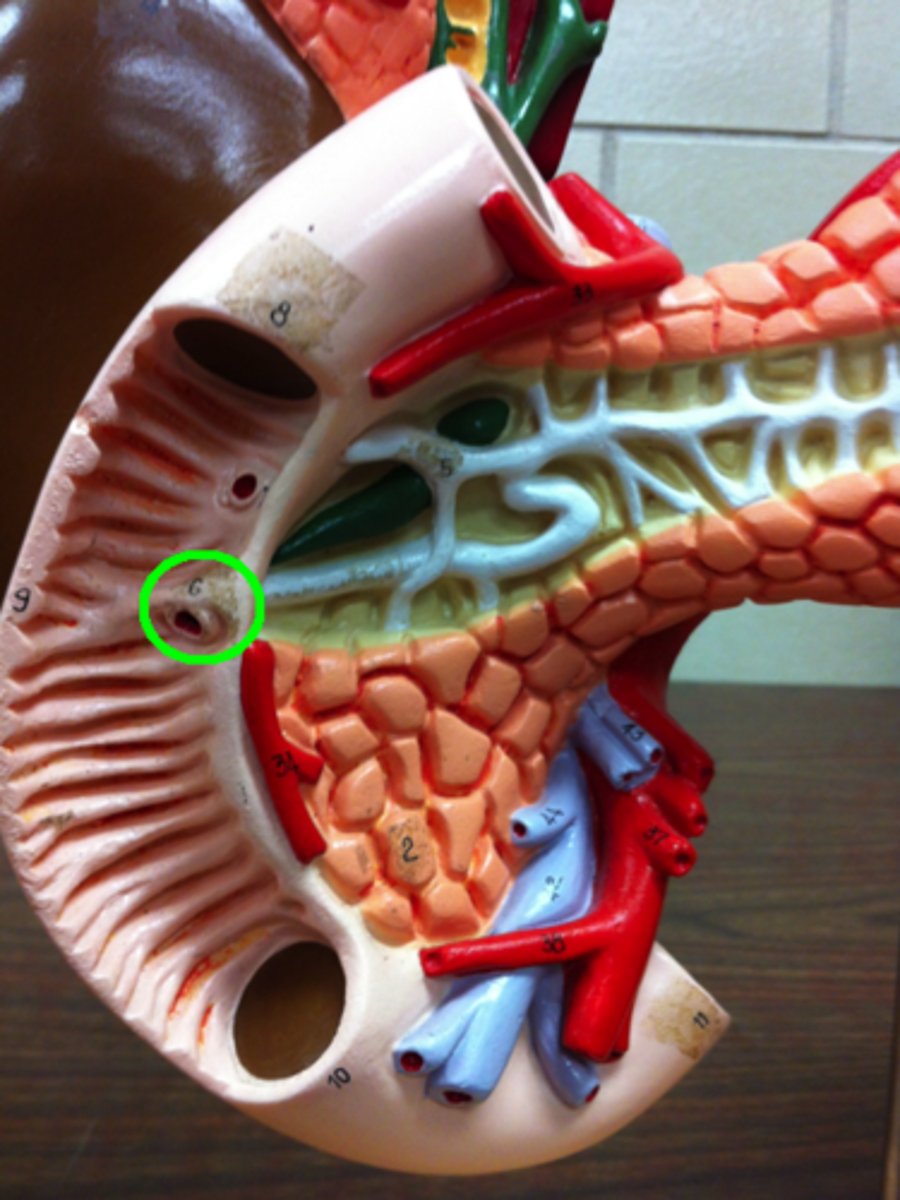

kidney

renal cortex

renal medulla

renal papilla

major calyx

minor calyx

renal pelvis

renal pyramids

ureter

renal columns

renal artery

renal vein

segmental

interlobar

interlobular

arcuate